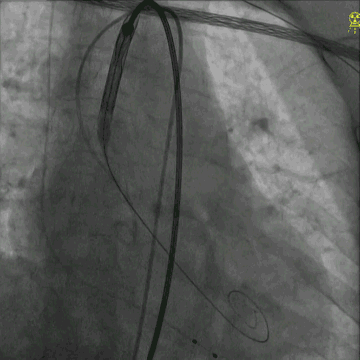

根据“杭州方案”,选择23mm NUMED球囊进行预扩,充分扩张后可见轻微腰征,无明显冠脉阻挡。依此瓣环上结构选择TaurusElite™ AV26主动脉瓣进行植入。

TaurusElite™可回收输送系统平稳柔顺的完成过弓、跨瓣并到位。